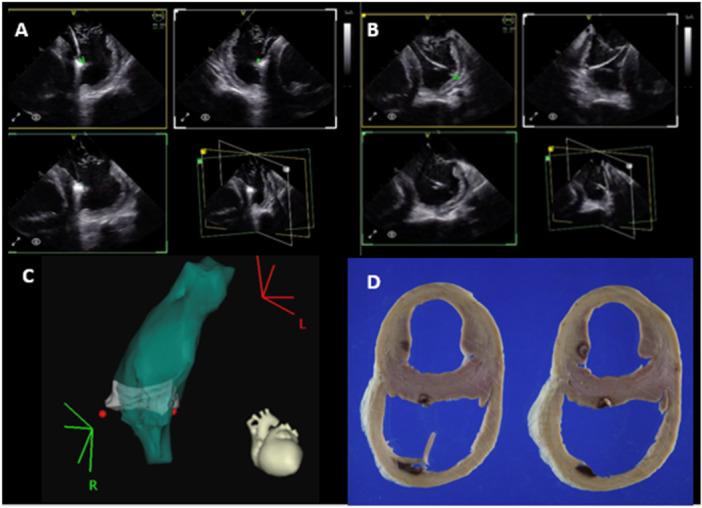

Intracardiac echocardiography (ICE) is an essential imaging modality for electrophysiology procedures, allowing intraprocedural monitoring, real-time catheter manipulation guidance, and visualization of complex anatomic structures. Four-dimentional (4D) ICE is the next stage in the evolution of the technology, permitting 360° rotation of the imaging plane, simultaneous multiplanar imaging, and volumetric acquisition, similar to transesophageal echocardiography (TEE). In this study, we report our experience with a novel 4D ICE catheter (NuVision, Biosense Webster) in structural electrophysiology procedures and difficult ventricular ablations in a swine preclinical model.

7 Yorkshire swine underwent 4D ICE (NuVision, Biosense Webster) imaging procedures and anatomical shells of the RV, LV, and LA were created on the CARTO mapping system. Ablation was performed on the RV moderator band and LV papillary muscles under imaging guidance with the 4D ICE catheter. Additional ICE images were obtained of the LAA to simulate placement of a left atrial appendage occlusion (LAAO) device. Triphenyl tetrazolium chloride was administered before euthanasia and hearts were harvested, fixed in formalin, and sectioned.

CARTOSOUND reconstruction was completed using the novel multiplane imaging software platform, allowing for creation of anatomy with minimal movement of the ICE catheter. Maps generated were similar to 3D reconstruction acquired in pre-procedure CT. Ablation lesions were successfully delivered to the LV papillary muscles and RV moderator band with excellent correlation between gross pathology, electroanatomic mapping (EAM), and ICE images. 2D, multiplane, and 3D volumetric images were obtained of the LAA with minimal catheter movement to simulate use for an LAAO procedure.

DISCUSSION

Intracardiac ultrasound has become an essential tool in the electrophysiology lab, especially for visualization of intracardiac structures in real time. 4D ICE is the natural progression of this technology, adding features previously only seen on TEE probes. In this preclinical study, 4D ICE was used to create CARTOSOUND shells with less catheter manipulation, which could decease procedural times and potentially decrease complications related to frequent manipulation of the ICE catheter. It was also placed in the left atrium to acquire multiplane and 3D rendered volumes of the left atrial appendage (LAA) similar to what would be required for an LAA occlusion procedure. This could be used as an alternative to TEE in LAAO procedures, potentially improving procedural efficiency and negating the need for general anesthesia. Additionally, it was used for real-time ablation guidance, specifically directly on the RV moderator band and LV papillary muscles. Multiplanar imaging allowed for more accurate catheter visualization and localization when targeting these complex 3D intracavitary structures.

心腔内超声心动图(ICE)是电生理手术中必不可少的成像方式,可进行术中监测、实时导管操作引导以及观察复杂的解剖结构。四维(4D)ICE是该技术发展的下一阶段,它允许成像平面进行360°旋转、同时进行多平面成像以及容积采集,类似于经食管超声心动图(TEE)。在本研究中,我们报告了在猪临床前模型中使用新型4D ICE导管(NuVision,Biosense Webster)进行结构电生理手术和困难心室消融的经验。

7只约克夏猪接受了4D ICE(NuVision,Biosense Webster)成像手术,并在CARTO标测系统上创建了右心室、左心室和左心房的解剖模型。在4D ICE导管的成像引导下,对右心室节制索和左心室乳头肌进行消融。获取了额外的左心耳ICE图像以模拟左心耳封堵(LAAO)装置的放置。在安乐死之前给予三苯基四氮唑氯化物,然后取出心脏,用福尔马林固定并切片。

结果

使用新型多平面成像软件平台完成了CARTOSOUND重建,在ICE导管移动最小的情况下创建了解剖模型。生成的图谱与术前CT获得的三维重建图谱相似。成功地将消融灶传递至左心室乳头肌和右心室节制索,大体病理学、电解剖标测(EAM)和ICE图像之间具有良好的相关性。通过最小的导管移动获取了左心耳的二维、多平面和三维容积图像,以模拟用于LAAO手术。

讨论

心腔内超声已成为电生理实验室中的重要工具,特别是用于实时观察心腔内结构。4D ICE是该技术的自然发展,增加了以前仅在TEE探头中看到的功能。在这项临床前研究中,4D ICE用于以较少的导管操作创建CARTOSOUND模型,这可以减少手术时间并可能减少与ICE导管频繁操作相关的并发症。它还被放置在左心房中以获取左心耳(LAA)的多平面和三维渲染容积,类似于LAA封堵手术所需的容积。这可以在LAAO手术中用作TEE的替代方法,有可能提高手术效率并消除全身麻醉的需要。此外,它用于实时消融引导,特别是直接用于右心室节制索和左心室乳头肌。多平面成像在靶向这些复杂的三维心腔内结构时允许更准确的导管可视化和定位。